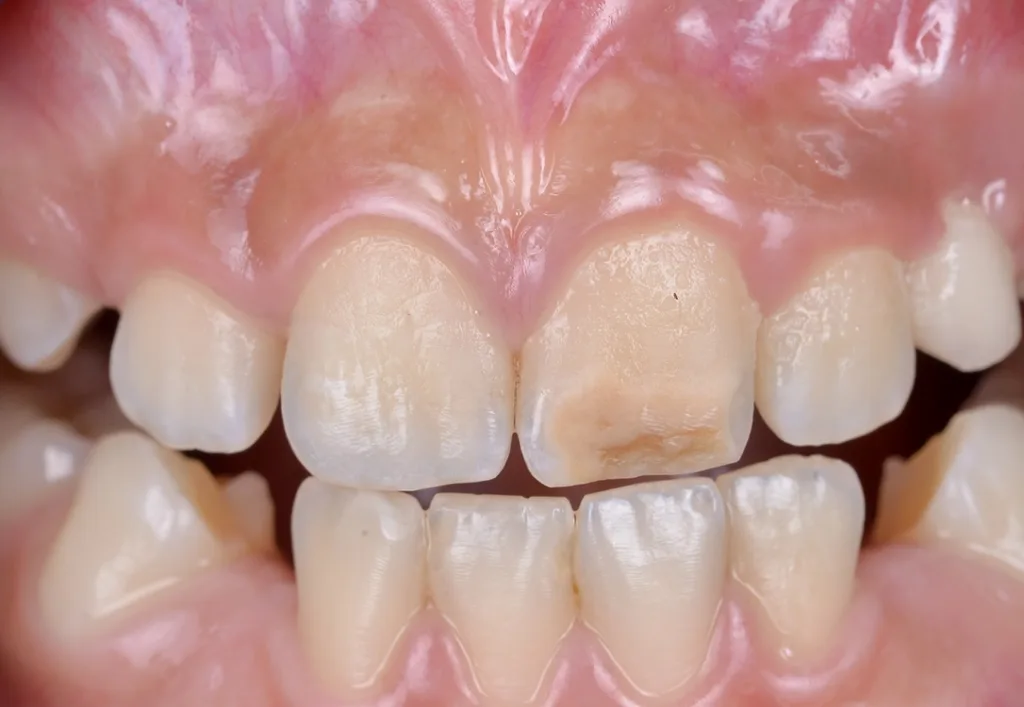

MIH-Läsionen an den Frontzähnen manifestieren sich häufig als klar abgegrenzte Opazitäten, deren Farbpalette von Weiß über Creme und Gelb bis hin zu Braun reicht. Diese farblichen Veränderungen sind ein wichtiger diagnostischer Hinweis auf die zugrundeliegende Strukturstörung des Zahnschmelzes. Besonders auffällig ist, dass die Intensität der Färbung mit dem Grad der Porosität und der strukturellen Beeinträchtigung des Schmelzes korreliert: Je dunkler und ausgeprägter die Opazität erscheint, desto höher der Restproteingehalt im Zahnschmelz, und desto höher ist das Risiko für posteruptive Substanzverluste, Frakturen und Hypersensitivitäten (Abb. 1). Die sorgfältige Beurteilung dieser visuellen Merkmale ist daher von zentraler Bedeutung für die Planung einer individuellen und effektiven Therapie, die sowohl funktionelle als auch ästhetische Aspekte berücksichtigt.

Um diesen Herausforderungen zu begegnen, wurden verschiedene modifizierte Behandlungsprotokolle entwickelt. Diese beinhalten unter anderem die Verlängerung der Infiltrationszeiten, das gezielte Abtragen der Oberflächenschicht (idealerweise als „selective surface removal“ unter Transilluminationskontrolle), um den Zugang des Infiltranten zum Läsionskörper zu ermöglichen, sowie eine Vorbehandlung mit oxidierenden Substanzen, um die Durchlässigkeit des Schmelzes für den Infiltranten zu steigern [17,18]. Darüber hinaus hat sich die optische Kontrolle der Infiltration mittels Transillumination als hilfreiches Instrument erwiesen, um den Infiltrationserfolg in Echtzeit besser beurteilen zu können und die Behandlung entsprechend anzupassen [17] (vgl. Fallbeispiel in Abb. 2).

![Abb. 2: Klinisches Fallbespiel [17]: a) Klinischer Ausgangbefund bei einem 12-jährigen Patienten,](https://dentalwelt.spitta.de/wp-content/uploads/2026/04/Abb2_A-1024x707.webp)